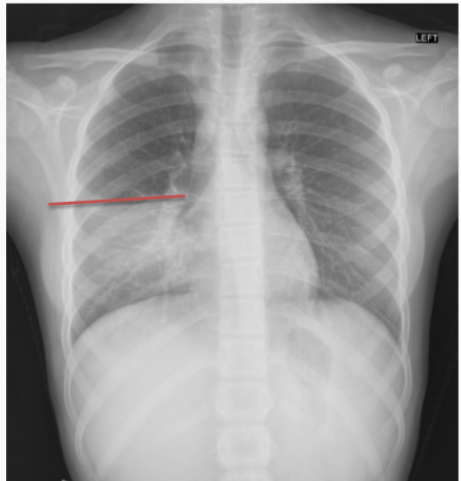

What is this patient presenting with?

Large pleural effusion (associated with “meniscus” sign)